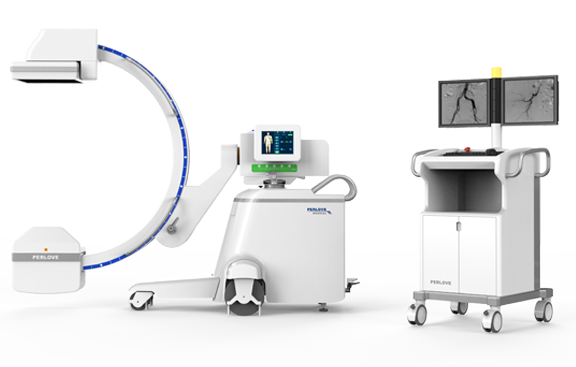

HF Mobile Digital C-arm System (Flat Panel Detector) PLX 7100A

Mobile design without modifying operating rooms:

• Meeting the surgical needs of about 80% large DSA equipment

• Small footprint compared with large DSA equipment

• Low operating costs without renovation and decoration of operating rooms

• Instant surgery share with flexible movement

• Convenient operation with plug-and-play

• Easy Installation: The operating room does not need to be modified and install ground rails and hangers, reducing the initial construction cost of intervention department.

• Mobile design: The equipment can be freely moved to any operating room, which greatly improves the utilization rate of the equipment.

• Small footprint: The equipment covers an area of only about 2 m2, saving the operating room space to place other equipment, which is convenient for the construction of a composite operating room.